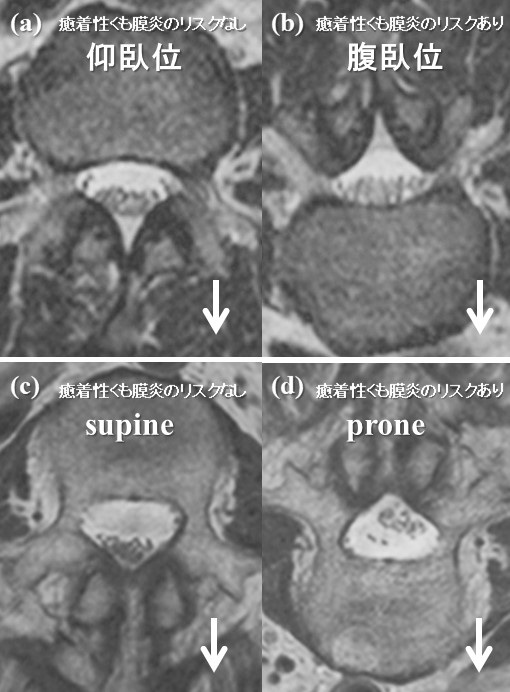

非侵襲的な画像撮影方法でくも膜下腔の神経の癒着を確認する2019-12-05 東京大学腰痛は日本人の患者さんが訴える最も多い疾患ですが、約20%が非特異的腰痛と呼ばれ、はっきりとした病因が分からないため適切な治療が難しい腰痛です。このなかに...